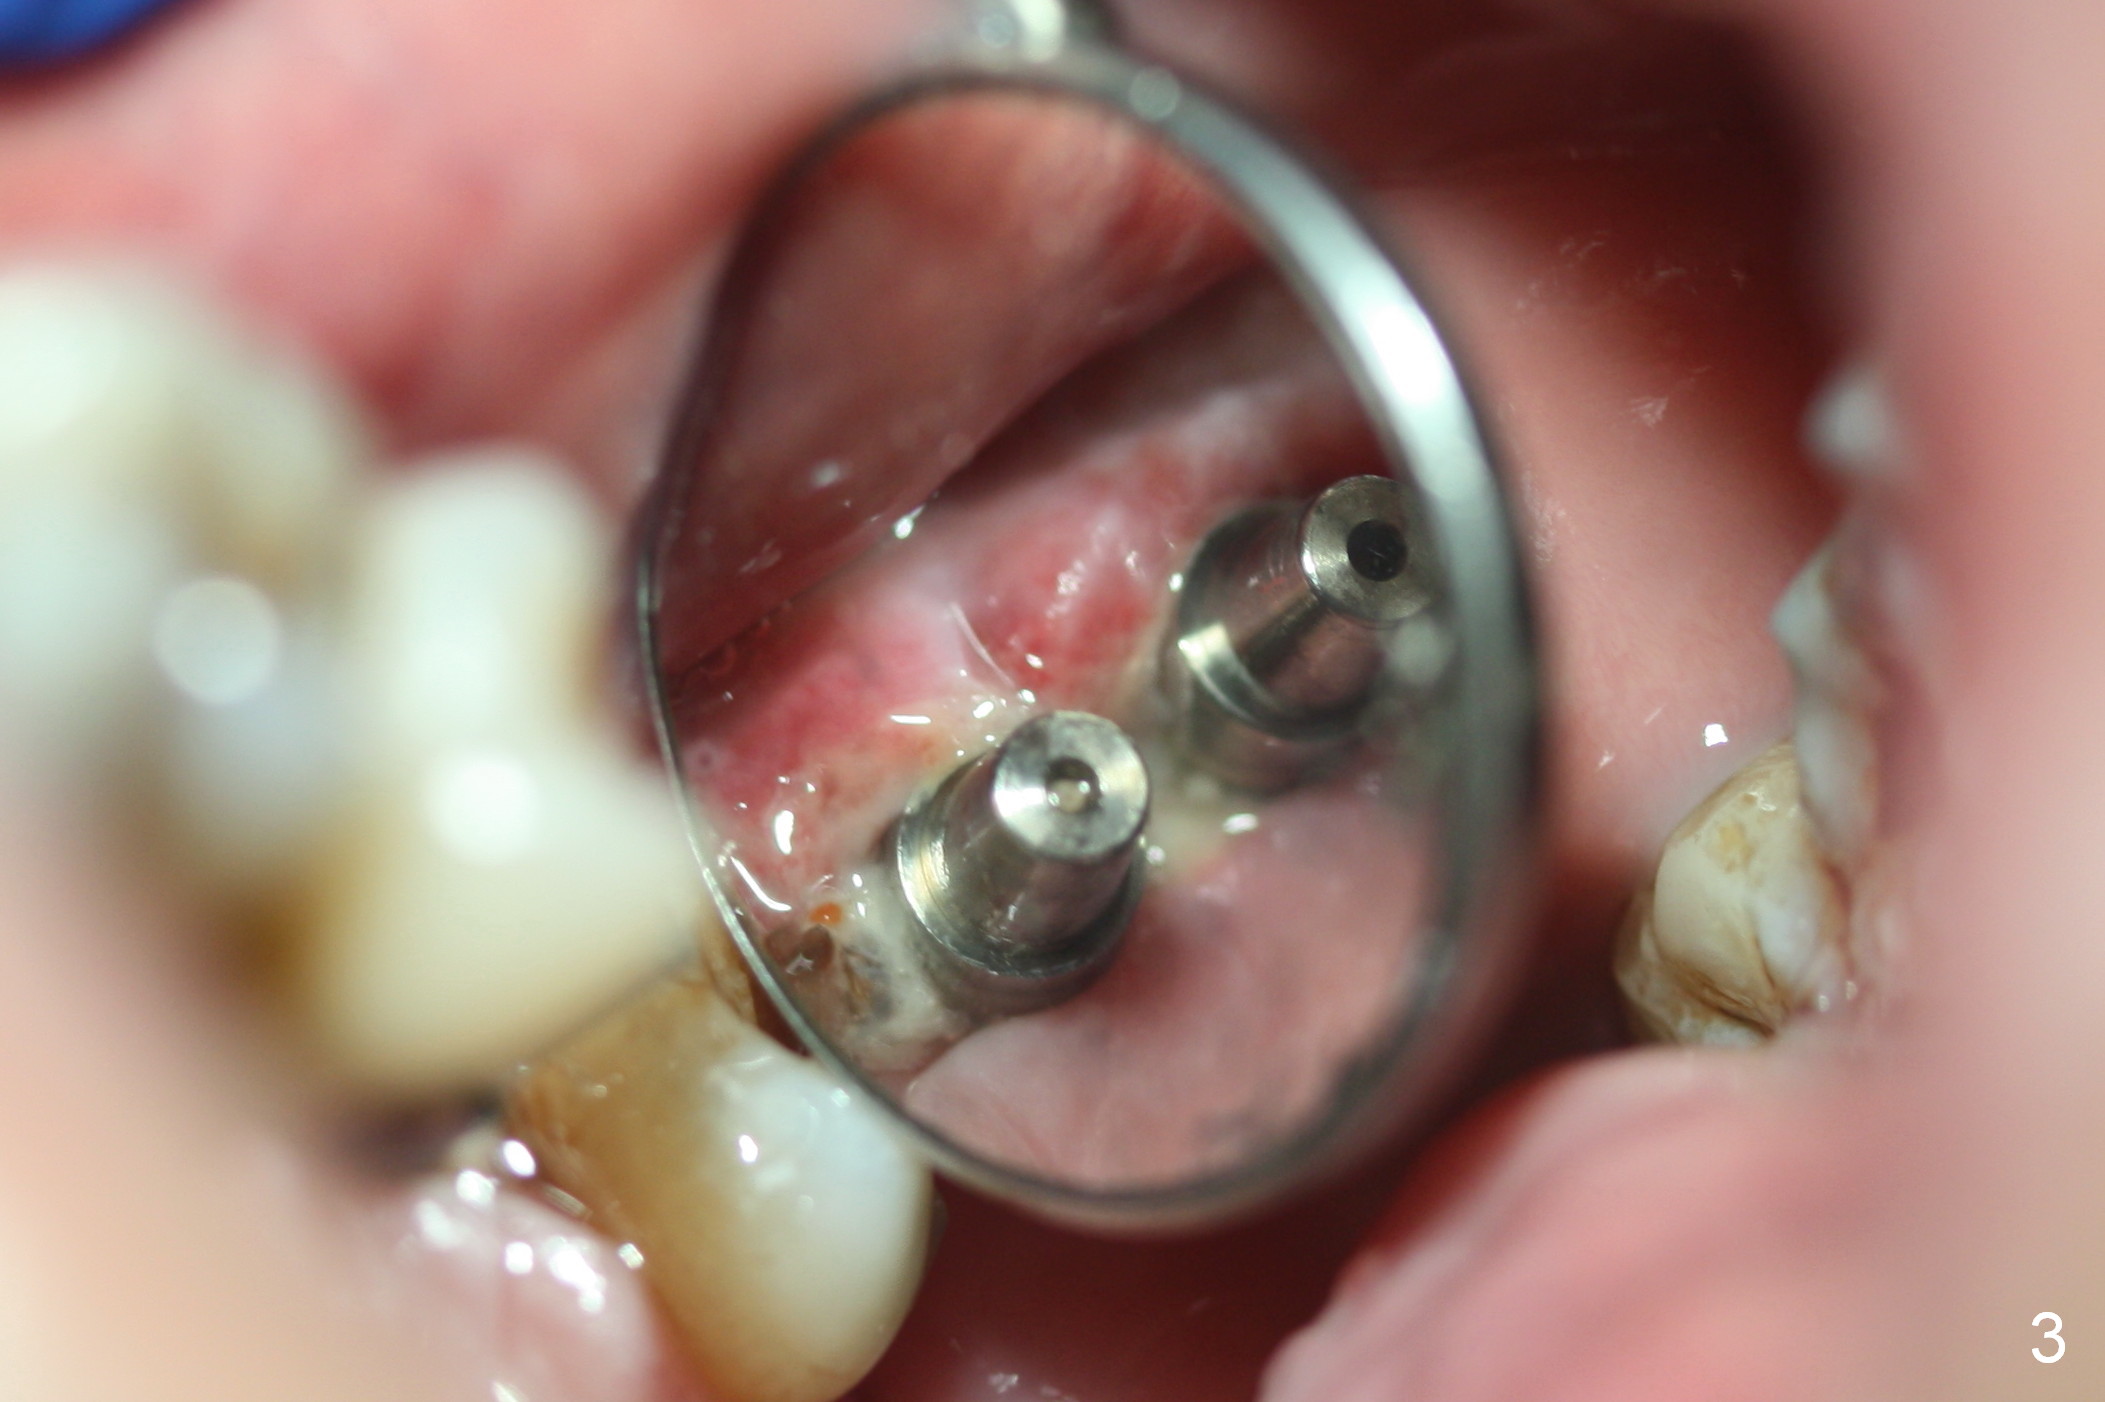

Mild to moderate hemorrhage is encountered as soon as incision is made for the lateral window. It is a concern prior to bone graft and implant placement. Hemorrhage appears to come from the sinus. Bleeding may wash away the graft. Therefore several pieces of Collagen Dressing are inserted into the sinus for hemostasis, followed by placement of Osteogen (Fig.1 *) and implant (5x14 mm, tissue-level). After placement of the 2nd implant, more Osteogen is placed buccal to the implants. Insertion torque is ~ 35 Ncm. Abutments (Fig. 2: 4x5 mm) are placed to hold perio dressing in place (no immediate provisional). In fact, the patient returns within 20 minutes postop because hemorrhage from the incision. Hemostasis is achieved with a few pieces of gauze in the buccal vestibule. Ice pack is recommended. By the evening, the patient reports minimal oozing. When perio dressing is lost 10 days postop, the wound opens (Fig.3). Later the wound heals. It appears that an immediate provisional provides the wound with temporary protection. The abutments without provisional is irritating to the soft tissue (the cheek in this instance). They have to be removed until the implants osteointegrate. PA taken 4 months postop shows the bone in the sinus surrounding the implants (Fig.4 *). The gingiva around the implants looks normal (Fig.5), although there is occasional and mild itching in the skin over the left sinus.